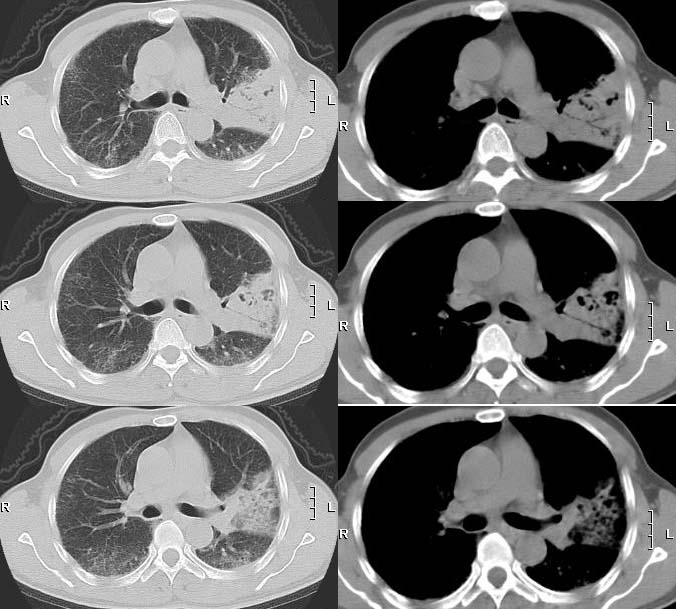

影像表现

(1)发生部位:炎性假瘤可发生在两肺的任何部位,但多位于肺的表浅部位,邻近胸膜处或者靠近叶间裂。可以跨叶生长,原因可能是跨叶浸润的炎症使得假瘤跨叶融合的结果。

(2)假瘤形态:炎性假瘤的形态不一,可呈圆形.椭圆形或类圆形,也可呈驼峰状或不规则图形。

(3)假瘤大小:多数假瘤的直径在2-4cm,也可大于5cm,少数甚至大于10cm.

(4)假瘤密度:炎性假瘤一般为中等密度,密度均匀。而脓性炎症形成的假瘤则有时可见小空洞。空洞可以单发也可多发。少数瘤体切开时可见脓性物。

(5)假瘤边缘:

①有假无假性包膜者边缘清楚。有的由于肿块不规则可表现分叶状。

② 无假性包膜者,假瘤周围有纤维化和多种细胞成分侵润,表现为片状、边缘模糊的团块状影。或有轻度的渗出性病变,边缘模糊,以组织细胞围增生型多见。有的假瘤周围还可以出现类似周围型肺癌的放射冠状表现。

(6)邻近改变:位于肺周边部的假瘤,其邻近胸膜可见局限性粘连增厚。位于近肺门区的假瘤,偶可阻塞支气管,形成肺叶不张而将假瘤包裹,甚似中央性肺癌,但不出现肺门或纵膈淋巴结肿大。